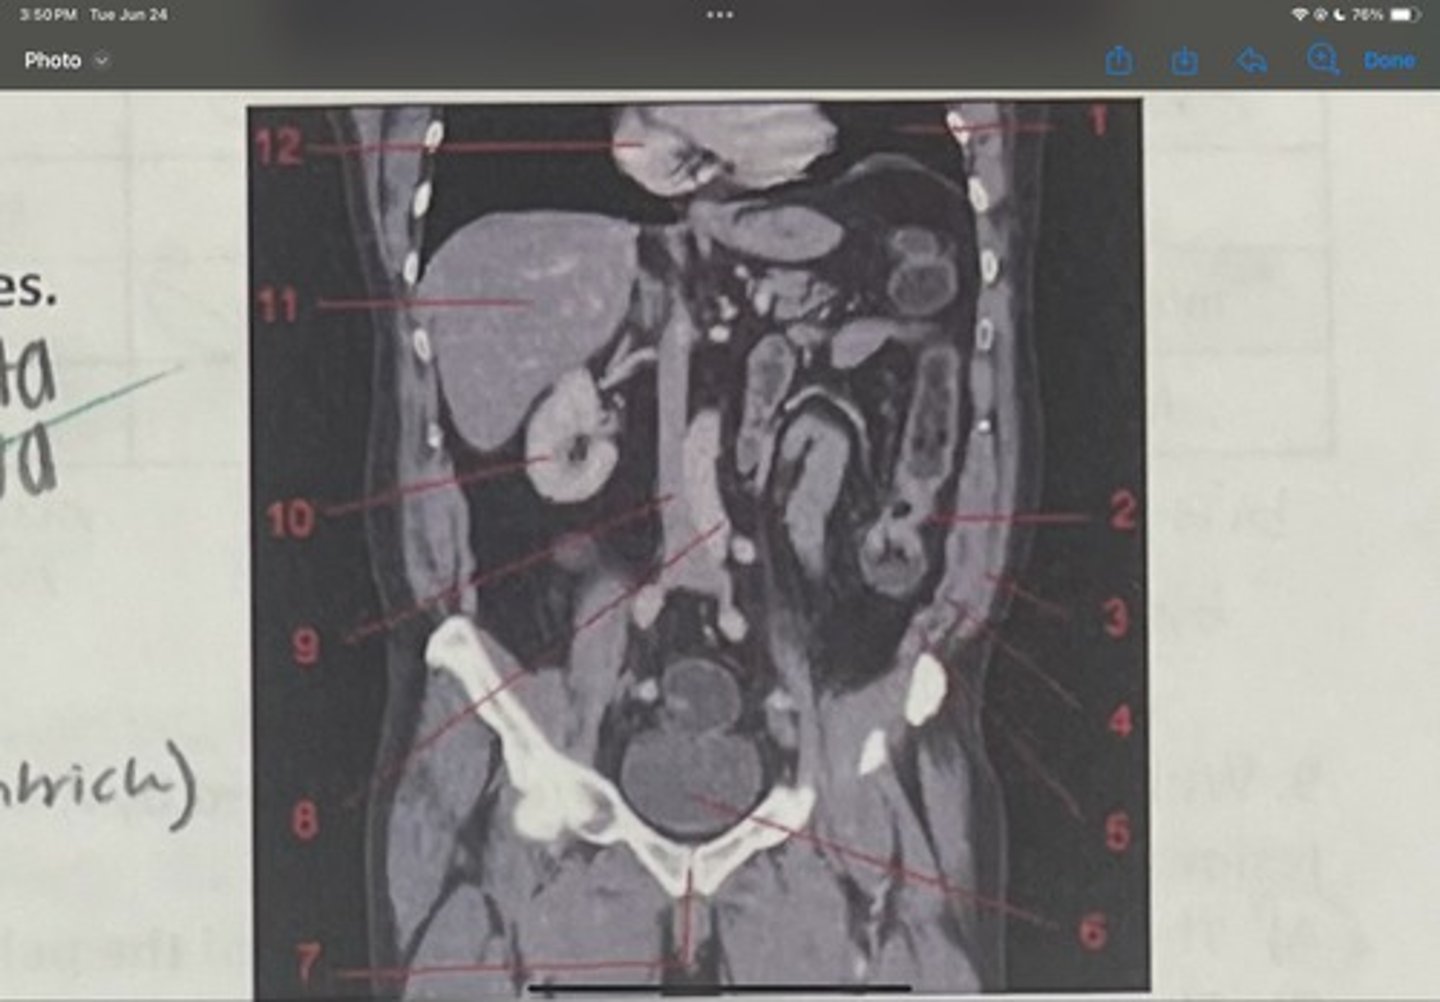

What is 1

Descending colon

What is 2

External oblique

What is 3

Internal obliques

What is 4

Transversus abdominis

What is 5

Bladder

What is 6

Pubic sysmphysis

What is 7

Abdominal aorta

What is 8

Inferior vena cava

What is 9

Right kidney

What is 10

Liver

What is 11

Heart (right ventricle)

What is 12

Subcostal nerve (T12)

What is 1

Illiohypogastric nerve (T12/L1)

What is 2

Illioinguinal nerve (L1)

What is 3

Genitofemoral nerve (L1-L2) ; on top of psoas

What is 4

lateral femoral cutaneous nerve (L2-L3)

What is 5

Femoral Nerve (L2-L4)

What is 6

Obturator nerve (L2-L4)

What is 7

Renal artery

What is the 1st one

Abdominal aorta

What is the 2nd one

Common iliac artery

What is the 3rd one

External iliac artery

What is the 4th one

Internal iliac artery

What is the 5th one

right common iliac artery blockage

What is the pathology of the image